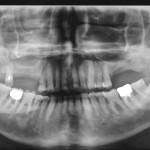

Autotrapianto di ottavo incluso a sostituzione di un settimo irrimediabilmente compromesso: case report

Luca Boschini1

Michele Melillo2

1Odontoiatra, libero professionista, Rimini

2Odontoiatra, libero professionista, Manfredonia (FG)

Specializzato in Chirurgia odontostomatologica presso l’Università G. D’Annunzio di Chieti

Riassunto

I trapianti dentali sono un capitolo...